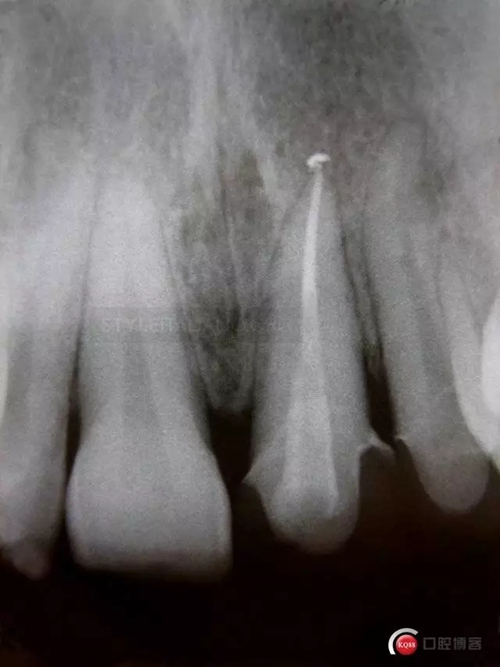

So, after the root canal treatment under the dam with correct pulp chamber opening, a cleaning of the cavity access and a root filling level control

617365.jpg